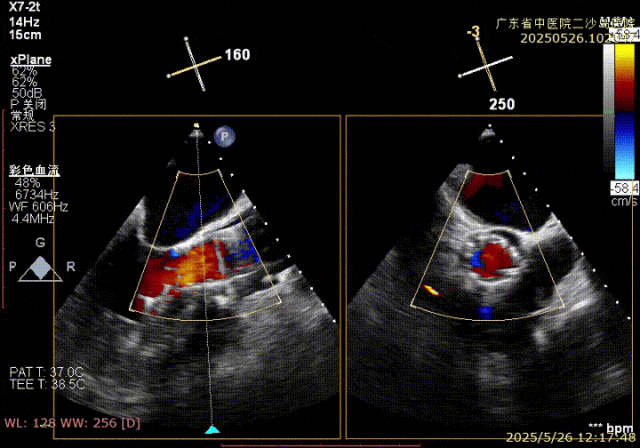

第二次释放前予以麻醉调整降低血压,稳定展开释放至工作位,即刻超声观察瓣架在无冠窦侧约处于瓣下2mm位置,但瓣周反流明显,瓣膜与周围组织存在间隙,评估稳定性过程中瓣膜再次上跳。

回收后进行第三把释放,考虑第二次工作位瓣膜上跳,尝试更深位置定位释放至工作位再行评估,因此初始定位瓣下4-5mm位置,释放至工作位约瓣下7-8mm深度,瓣膜压缩成桶状,造影反流较少,超声观察瓣周贴合较好,但考虑深度较深,瓣膜多次回收后压缩评估可能存在误导,计划更换AV31瓣膜。

更换AV31新瓣膜后,定位瓣下3-4mm左右开始释放,高速起搏血压下降至70mmHg后,开始快速匀速释放,展开过程稍上移并锚定。

工作位多角度评估深度,约瓣下3mm左右,无冠窦侧压缩内凹明显。

超声评估,深度符合DSA评估深度,约瓣下4mm左右,存在明显无冠窦侧压缩,准备进行瓣膜脱钩释放。

TauruMax脱钩释放阶段优势明显,脱钩过程稳定易控制,调弯后良好的同轴,脱钩后无位移,释放后,无冠窦侧仅1mm自同轴调整。